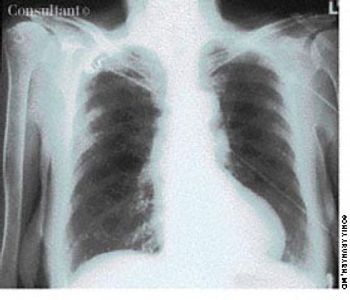

For the past 2 days, a 30-year-old man had experienced scant hemoptysis. He had also lost a significant amount of weight-5 kg (11 lb)-over the last 2 months. The patient, a recent emigrant from Ecuador, had no history of tuberculosis (TB) or of exposure to this disease, and he had not been skin tested with purified protein derivative (PPD). He denied exposure to risk factors for HIV infection.

A previously healthy 51-year-old man presented with weight loss and poor appetite of 2 months' duration. He was heterosexual and had many sexual partners. Except for a temperature of 38.3°C (100.9°F) and left basal rhonchi, results of physical examination were normal. A chest radiograph and CT scan, as seen here, showed large cavitary lesions in the lower left lobe.